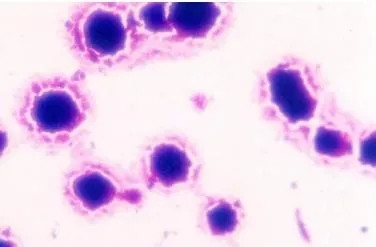

支原体(mycoplasma)是一类没有细胞壁、高度多形性、能通过滤菌器、可用人工培养基培养增殖的最小原核细胞型微生物。由于能形成丝状与分枝形状,故称为支原体。

支原体广泛存在于人和动物体内,大多不致病,对人致病的支原体主要有肺炎支原体、溶脲脲原体、人型支原体、生殖器支原体等。